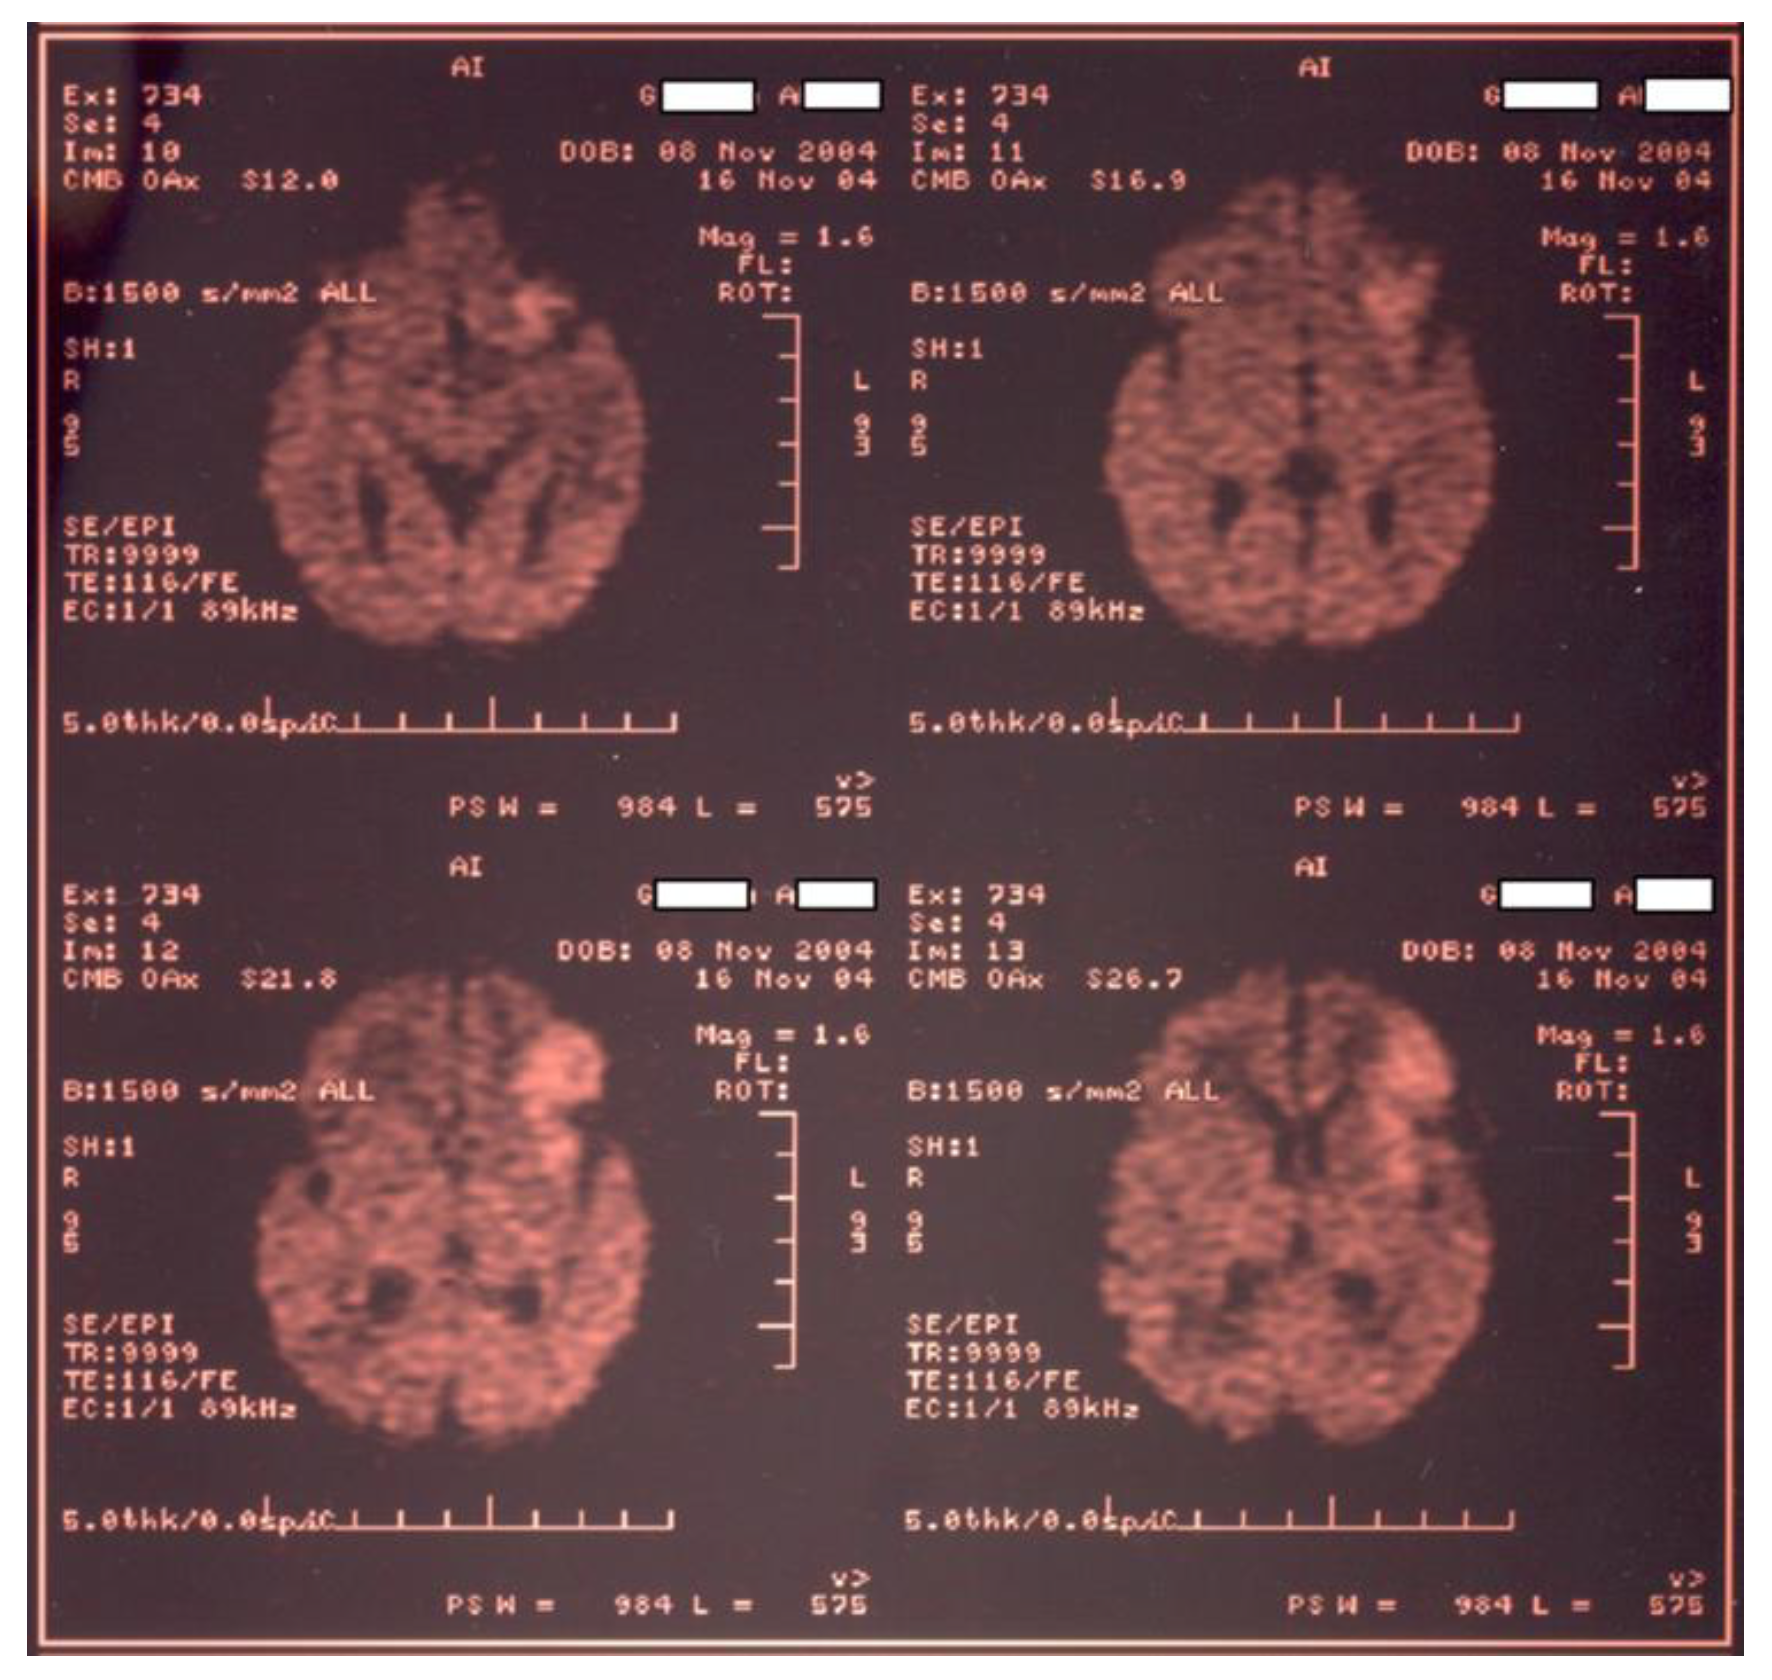

Newborn #1 was born at 36-37 weeks of gestation, 3000g/50cm, female, first child of a healthy mother, from an uneventful pregnancy, extracted by caesarean section for premature rupture of membranes, Apgar score 9, smooth transition to the extrauterine environment, normal clinical examination after birth; baby develops at 36 hours of life tonic-clonic seizures of the left hemibody associated with cyanosis, apnea and bradycardia and was admitted into the NICU, was tested for metabolic causes of the seizures, lumbar puncture and inflammatory panel and bacteriologic tests were performed and Phenobarbital was started. Because of recurrent apneic spells respiratory support was initiated and imagistic investigations were ordered. Head ultrasonography raised suspicion of a large right frontal-parietal infarction confirmed later through Magnetic Resonance Imaging (MRI). Echocardiography revealed no abnormalities. Laboratory tests were all within normal limits except a mild thrombocytopenia (105000/mmc).

Figure 1. CT examination for newborn #1.

Figure 2. MRI examination for newborn #1 confirms large right frontal-parietal infarction.

Within differential diagnosis, we considered: maternal chorioamnionitis, hypoxic ischemic encephalopathy, vascular malformations, cardiac lesions, trauma and a hereditary coagulopathy. We performed molecular tests for both mother and infant that revealed heterozygote G1691A mutation on the gene responsible for synthesising factor V Leiden. A less frequent condition related to ischemic stroke in children and adults is sickle cell disease, although not documented in newborns, was also excluded [24,25].

Most perinatal strokes are ischemic and affect the left cerebral hemisphere, in the territory of the middle cerebral artery [26]. In our case, the infarct was in the frontal-parietal right cortical region. We could not identify in this case any of the supplementary risk factors for thrombosis.